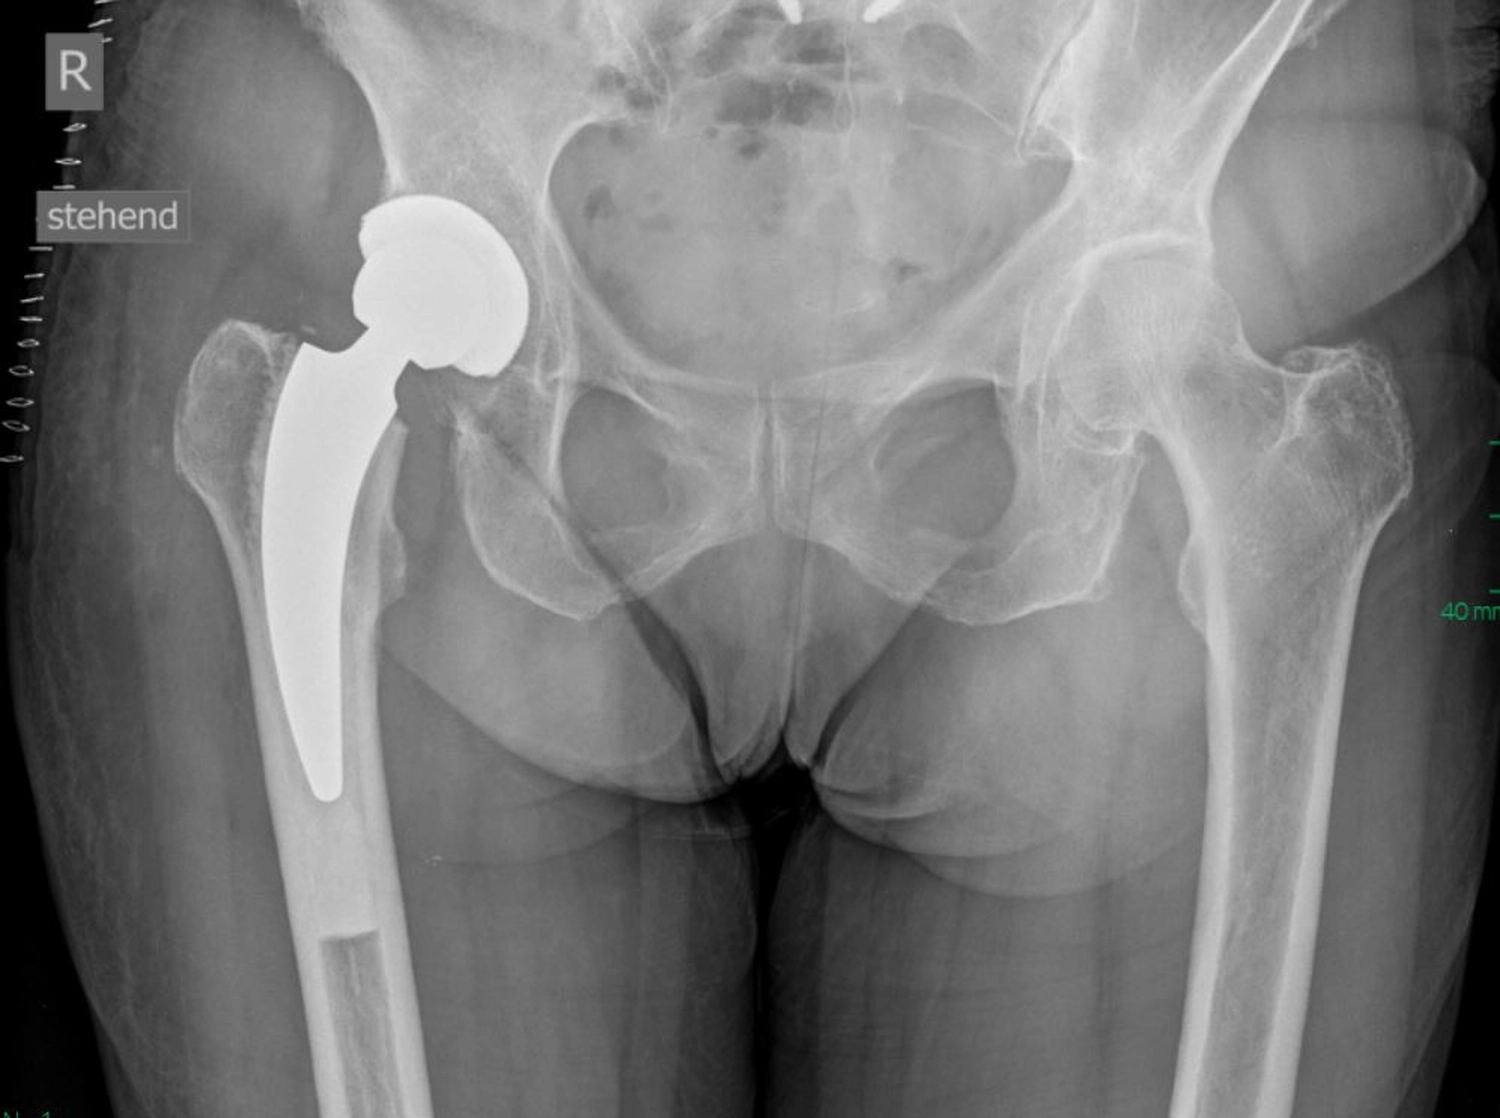

Ein künstliches Hüftgelenk ersetzt die geschädigten Teile des natürlichen Gelenkes. Es besteht aus mehreren Komponenten, die gemeinsam ein neues, stabiles und bewegliches Gelenk bilden. Die Pfanne wird in das Becken eingesetzt. Der Schaft wird im Oberschenkelknochen verankert. Der Prothesenkopf sitzt oben auf dem Schaft und bildet die „Kugel“ des Gelenkes und bewegt sich reibungsarm in der Pfanne.

Je nach Knochenqualität und Alter der PatientInnen werden zwei Verfahren angewendet.

Bei der zementfreien Prothese werden der Schaft und die Pfanne fest eingepresst und eingeschlagen. Der Knochen wächst in die aufgeraute Oberfläche ein und fixiert die Prothese dauerhaft.

Bei der zementierten Prothese werden die Prothesenteile mit einem speziellen Knochenzement befestigt. Der Vorteil besteht in einer sofortigen Stabilität, besonders geeignet bei älteren oder osteoporotischen PatientInnen.

Daneben gibt es sog. Hybridverankerungen, z. B. Pfanne zementfrei, Schaft zementiert.

Moderne Prothesen, wie wir sie hier in Stenum verwenden, sind so konstruiert, dass sie reibungslos, stabil und langlebig funktionieren, meist über viele Jahre bzw. Jahrzehnte (15–20 Jahre).

Dank der modernen Materialien und gewebeschonenden Techniken des Einbringens, (minimalinvasiver Zugang) ist die Hüft-TEP heute ein sehr erfolgreicher Eingriff, der vielen Menschen eine deutliche Verbesserung ihrer Lebensqualität ermöglicht.